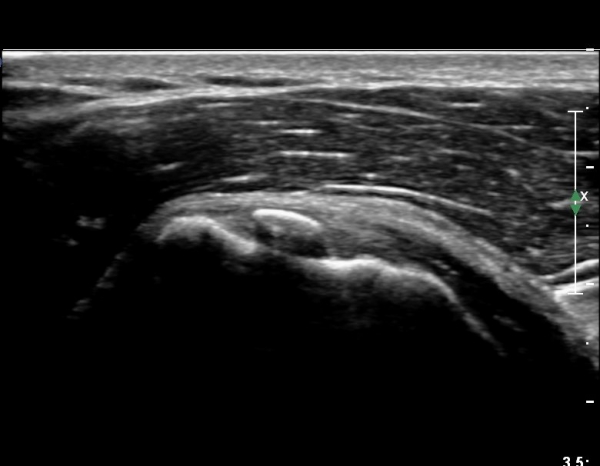

ÃÊÀ½ÆÄ ¼Ò°ß :  ÀÌµÎ¹Ú±Ù°Ç È¾´Ü¸é°Ë»ç¿¡¼­ ¼Ò°áÀý ºÎÂø °ß°©Çϱٰdz» °í¿¡ÄÚ ¼®È¸È­ µ¢¾î¸®°¡ °üÂûµÈ´Ù(»çÁø 1).

°ß°©ÇÏ±Ù°Ç È¾´Ü¸é°Ë»ç»ó ¼Ò°áÀý ÇÊÁú°ñº¯È­¿Í °ß°©ÇÏ±Ù°Ç Áߺο¡ °í¿¡ÄÚ µ¢¾î¸®°¡ °üÂûµÇ°í

¼®È¸ À§ÂÊ(¸Ó¸®ÂÊ)ÀÇ ÈûÁÙÀÇ Àú¿¡ÄÚ º¯È­°¡ °üÂûµÈ´Ù(»çÁø 4, 5).